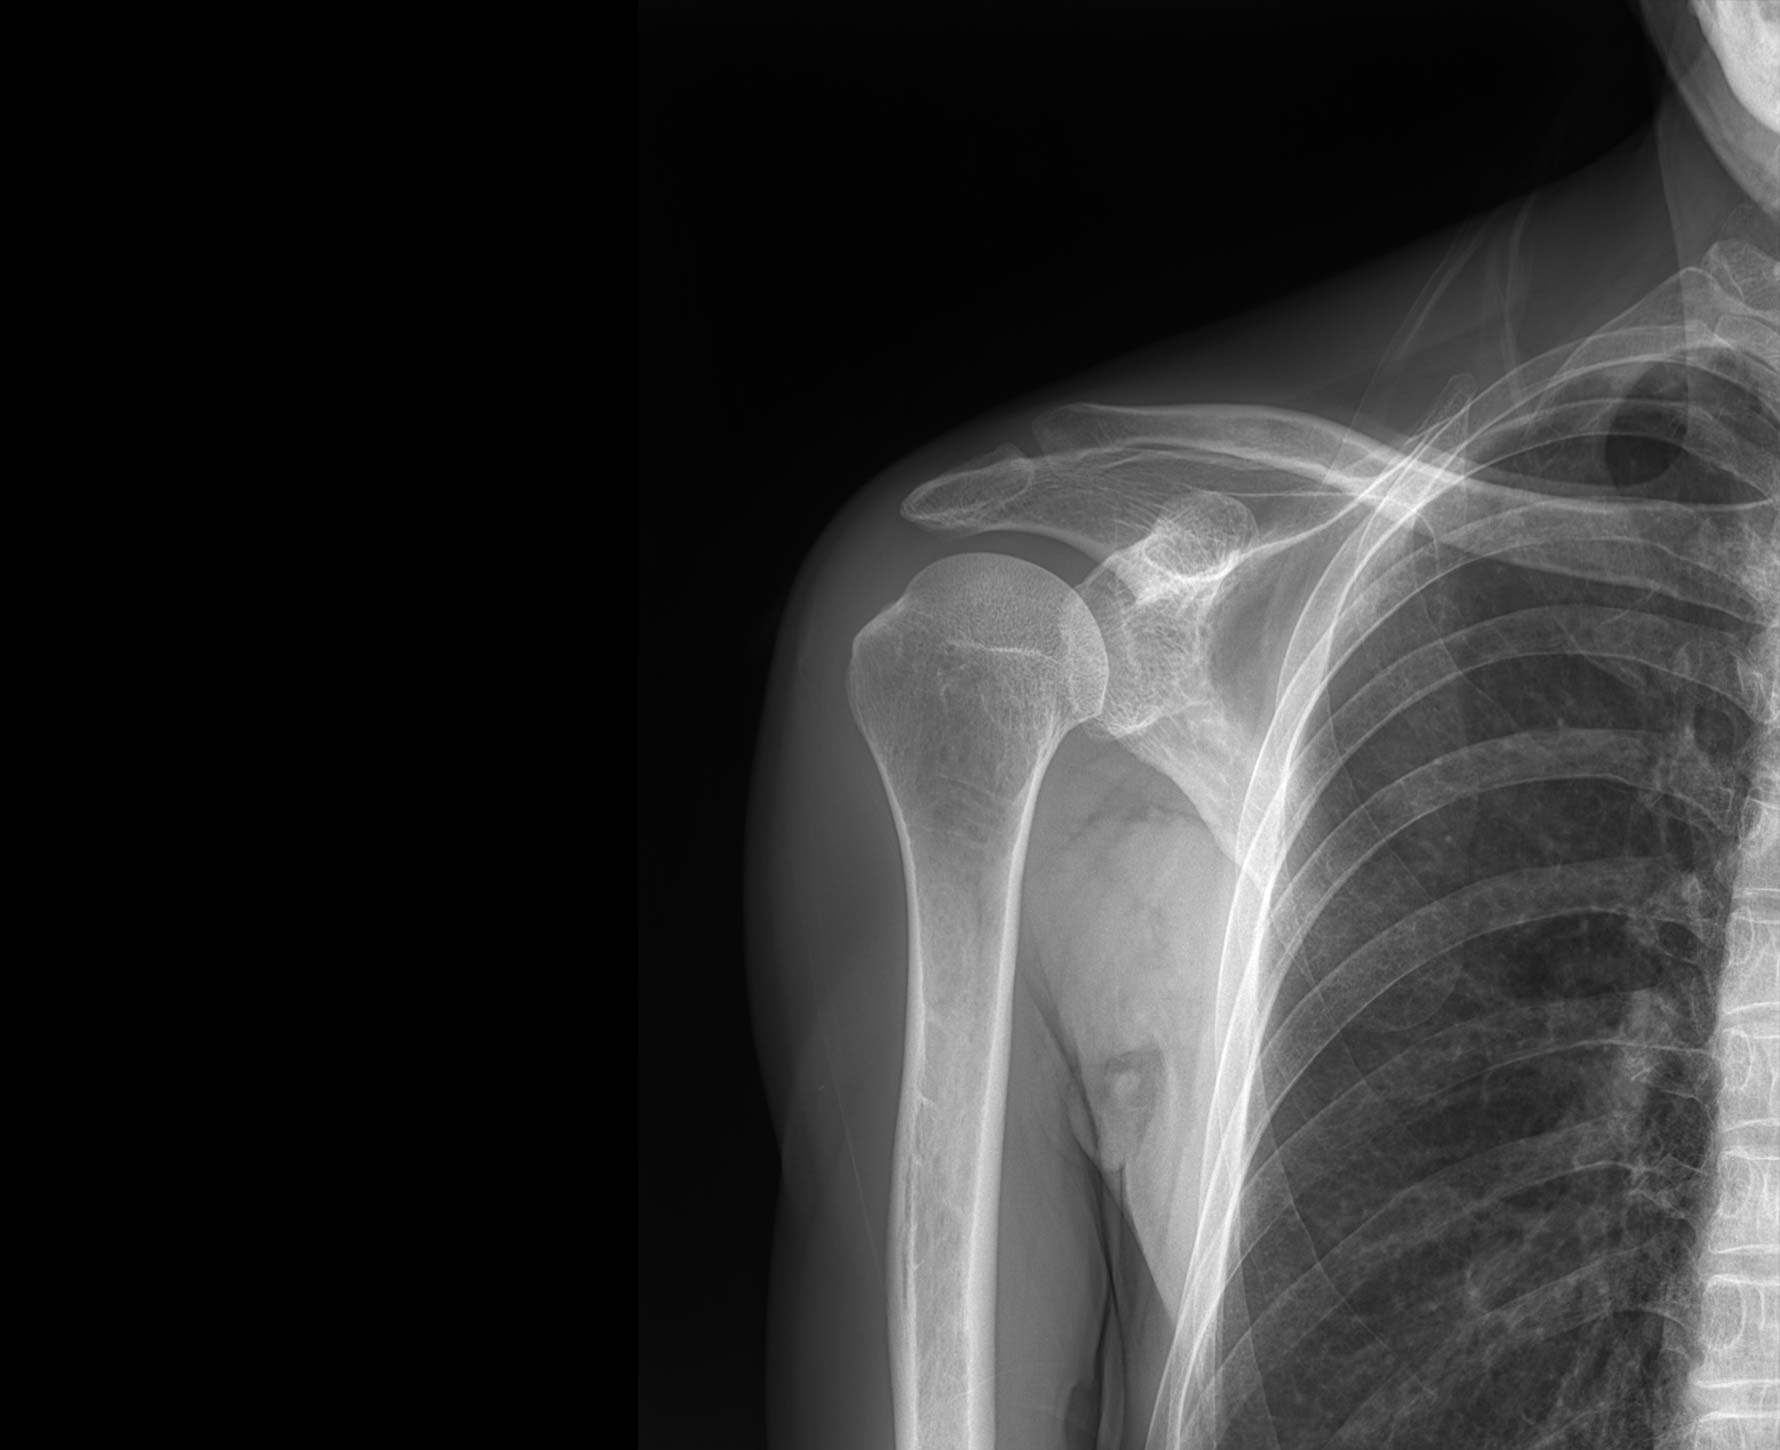

• 拍片

适用于全身各部位摄影

(常规摄影和特殊摄影)